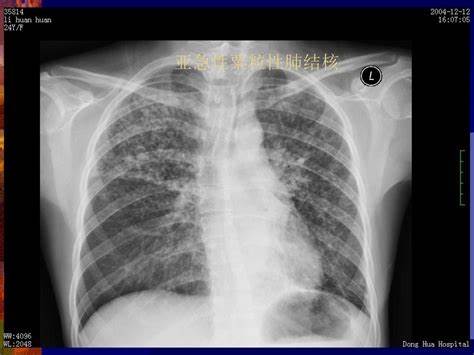

另外一个病例,男性,46岁,爱游泳,平时身体很棒,因发热、咳嗽就诊,肺部CT提示右上肺结核灶。

入院后,检查发现白细胞高,C反应蛋白高,痰多,呈黄色或灰色。

痰检阴性、T-SPOT阳性、PPD阴性。

医生的诊断是打了问号的肺结核和肺炎,正要抗结核治疗,患者也准备吃药。

肺结核是由结核分枝杆菌引起的传染病,主要通过空气、飞沫经呼吸道传染。

肺结核多表现为慢性病程,症状有时候很不典型。如果在患者的痰或病理组织中没有找到结核分枝杆菌,诊断有时候比较困难。